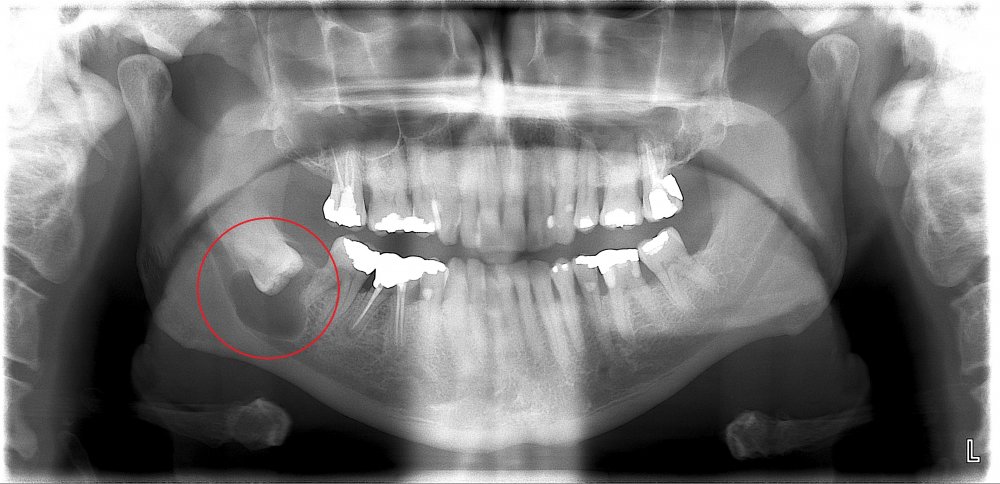

Normal halda insanın diş sırasında hər çənədə iki ədəd olmaqla, ümumilikdə dörd agıl dişi mövcuddur. Ağıl dişinin çıxması bəzi şəxslərdə heç bir kliniki əlamət və ya şikayətə səbəb olmasa da, bir çox hallarda müəyyən kliniki əlamətlərlə öyünü biruzə verir. Bu əlamətlər əsasən çənənin arxa tərəfində təzyiq, çənəni açıb baglama əsnasında agrı və məhdudlaşma kimi özünü göstərə bilir. Bu hallarda mütəxəssis konsultasiyasının önəmi olduqca böyükdür. Belə ki müayinə zamanı cərrah-stomatoloq kliniki və radioloji dəyərləndirmə apararaq dişin dogru pozisiyada yerləşib yerləşmədiyi, dişləmə çıxma ehtimalını, agıl dişinin çənəyə görə ölçüsü və çənə darlıgı kimi durumları dəyərləndirərək tətbiq edilməli olan müalicə taktikasını müəyyən edir.

- Retensiyon ağıl dişinin spontan və ya ortodontik olaraq dişləmə çıxma ehtimalı mövcud deyilsə

- Ağıl dişinin ətrafında iltihabi proses və ya xoş/bədxassəli törəmə mövcuddursa və prosesin müalicəsi ağıl dişinin çəkilməsini tələb edirsə

- Ağıl dişi qonşu dişdə karies, sorulma, parodontal problemlər və s. yaradırsa